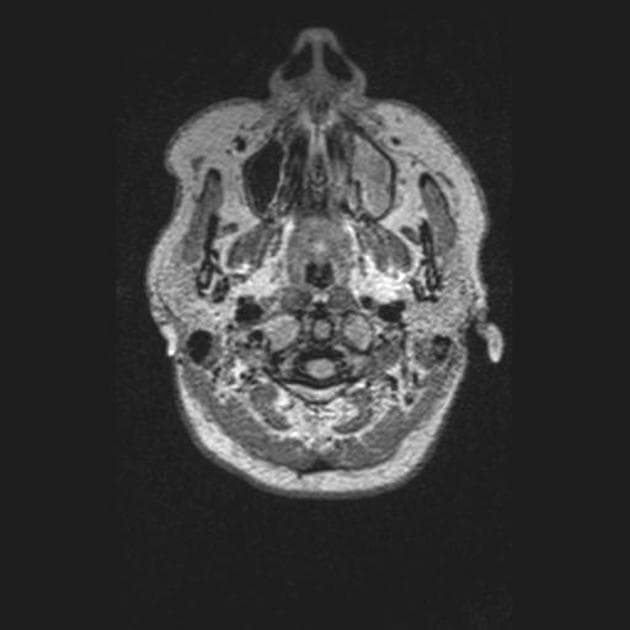

Axial T2

- Ghi nhận nhiều tổn thương kích thước thay đổi, ở hai bên tại vùng quanh não thất (periventricular), vùng cận vỏ (juxtacortical), vùng tiểu não, chi sau bên trái của bao trong (left posterior limb of the internal capsule) và cánh cầu bên trái (left brachium pontis).

- Các tổn thương vùng quanh não thất định hướng vuông góc với não thất (Dawson fingers).

- Các tổn thương biểu hiện tín hiệu giảm trên T1, tăng tín hiệu trên T2 và FLAIR.

- Một số tổn thương cho thấy hiện tượng T2 shine-through (tín hiệu tăng trên DWI và ADC tăng), trong khi một số khác, chủ yếu là các tổn thương quanh não thất, biểu hiện tín hiệu sáng dạng viền trên DWI với ADC ngoại vi giảm (hạn chế khuếch tán thật sự – true restriction).

- SWI phát hiện dấu hiệu tĩnh mạch trung tâm (central vein sign) tại tổn thương ở chi sau của bao trong (PLIC).